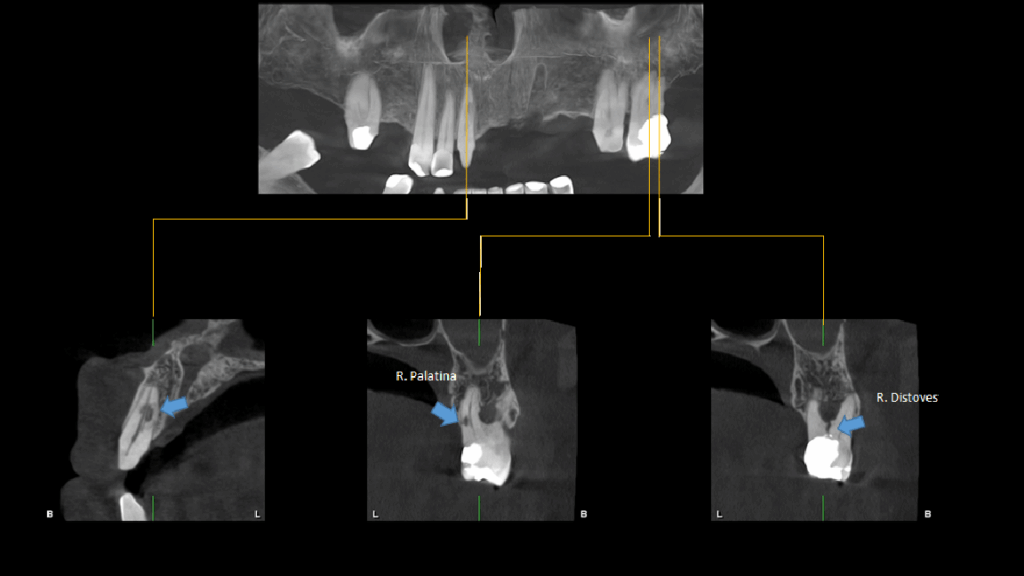

A la evaluación de la tomografía cone beam de campo mediano (FOV = 10 x 10) se observa en la pieza 11 la presencia de una imagen hipodensa de forma irregular localizada a niel de tercio medio radicular y que se compromete la dentina radicular por mesial y palatino, asimismo se observa la pieza 27 que además de la restauración presenta una imagen hipodensa en raíz palatina a nivel de tercio medio radicular y finalmente un trazo de fractura vertical por distal que compromete la zona de furcación y ocasiona un proceso osteolítico interradicular.

CORTES TANGENCIALES